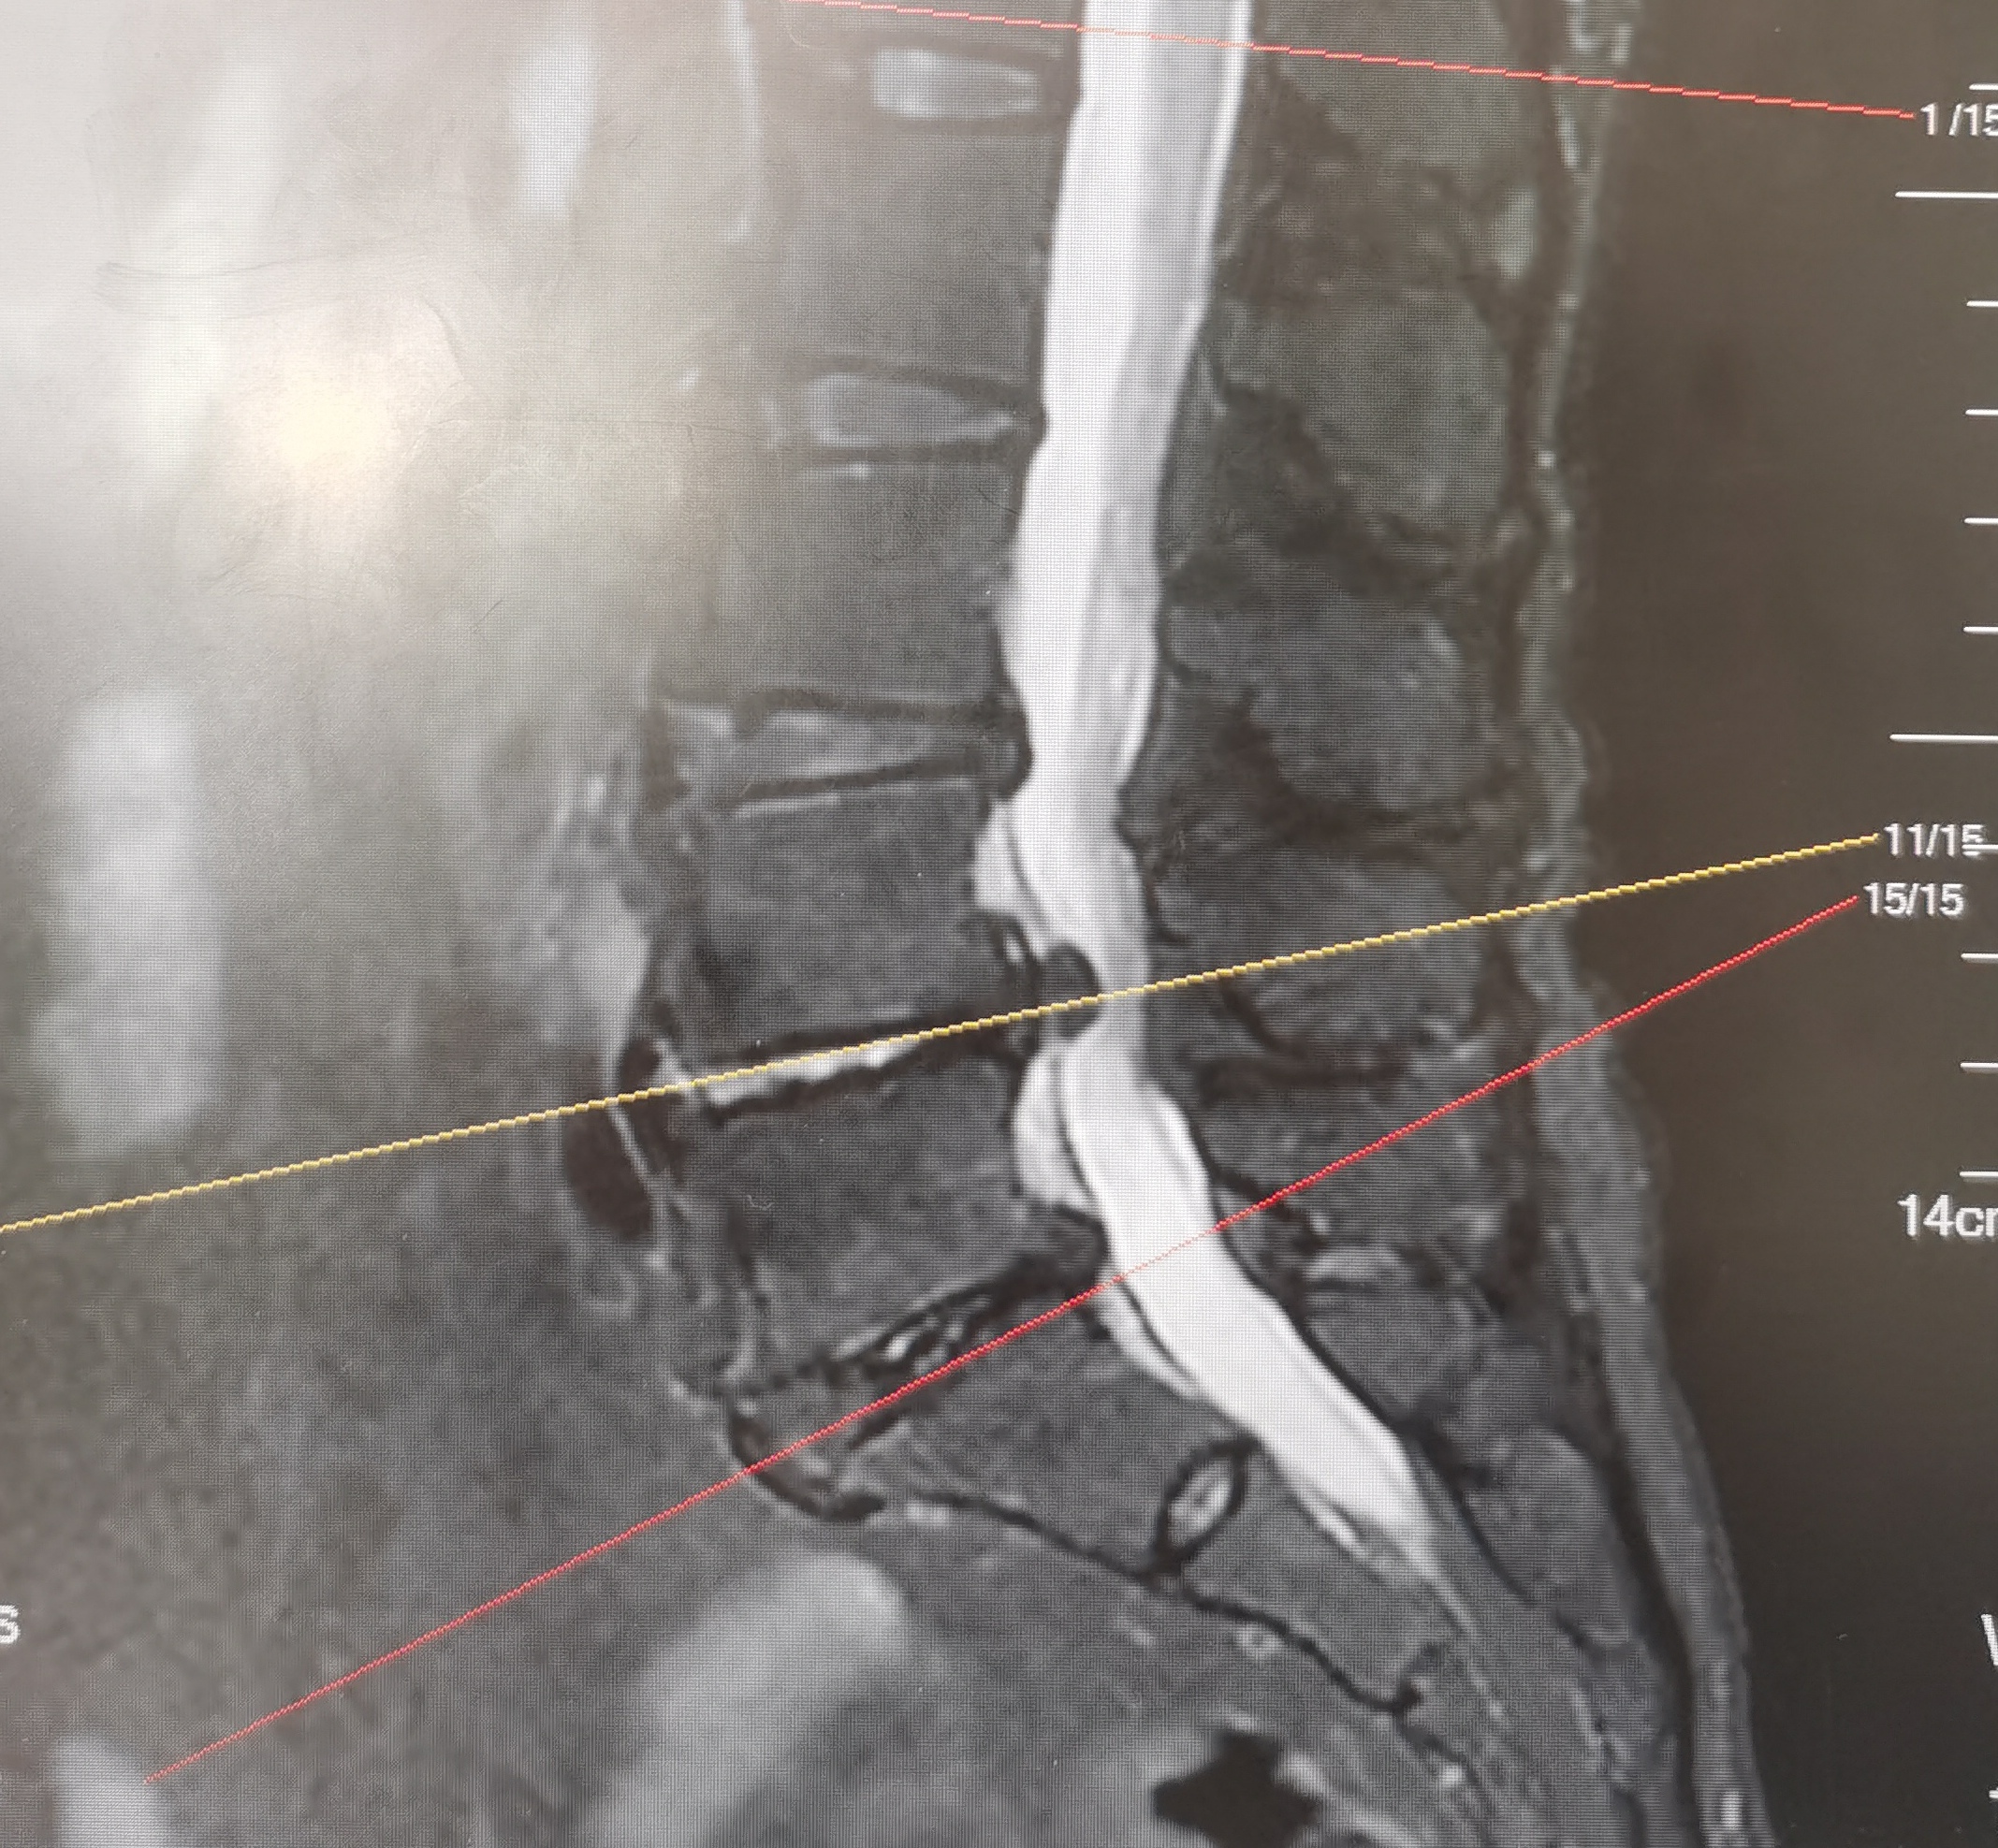

腰4、腰5椎体叠成“罗汉塔”,腰4/5正好卡在“承重枢纽”。弯腰搬重物时,这个位置承受的压力能达到体重的3-5倍——相当于让腰椎常年扛着一袋水泥。椎间盘里的髓核本是缓冲震动的“果冻垫”,但经年累月的劳损会让外层纤维环裂开,髓核一旦“漏”出来,首当其冲压迫腰5神经根。

但必须清醒:对于已经游离的髓核,靠保守治疗的成功率不到10%。拖过4周还硬扛,神经功能可能像被掐断的水管,永远流失30%的“水流”。